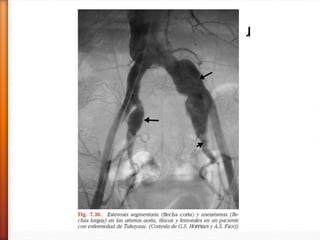

» 6. Arteriografía anormal.Estrechamiento u oclusión arteriográfica de toda la aorta

sus ramas primarias o grandes arterias en la zona próximal de extremidades

superiores e inferiores, no debida a arte- rioesclerosis, displasia fibromuscular o

causas similares; cambios habitualmente focales o segmentarios. Para etiquetar a

un paciente de Arteritis de Takayasu deben estar presentes al menos 3 de estos 6

criterios.

˃ Arteriografía convencional : estenosis vasculares, circulación

colateral, aneurismas.